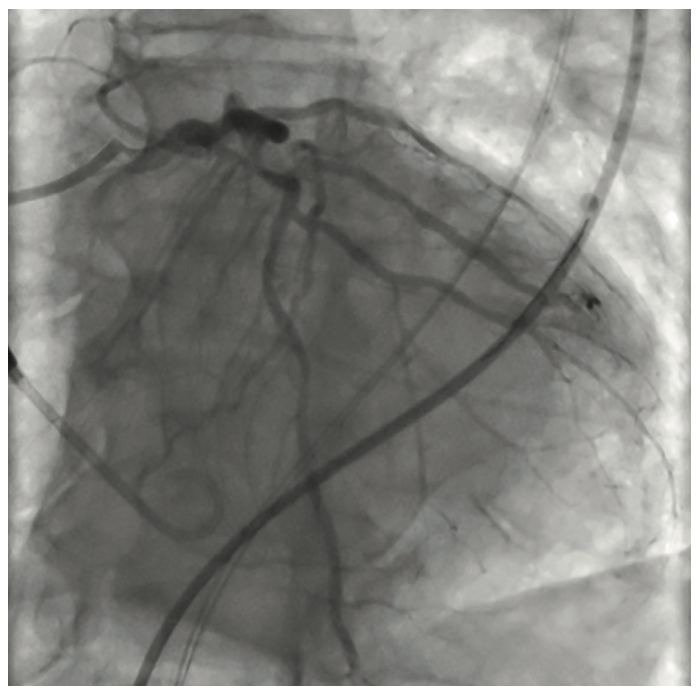

The initial interventional attempt via a transradial approach was unsuccessful due to significant vessel tortuosity. Therefore, a high risk protected PCI was attempted via left femoral access using an Impella 2.5L device (Abiomed) for left ventricular support. The Impella 2.5L was placed via the right femoral access. Before the engagement of coronary arteries, the patient had deteriorated clinically with hypotension and Impella support dropping to 1.4L. Subsequently, the patient went into VT/VF arrest, requiring cardiopulmonary resuscitation (CPR). The patient was emergently intubated. During active CPR and VT storm, selective injections of the left main coronary artery were performed, revealing total thrombotic occlusion of distal left main artery. The patient underwent multiple percutaneous transluminal coronary angioplasties of the left main, ostial and mid LAD, and LCx (OM1) lesions. This was then followed up with stenting of the mid left main into the ostial LAD and LCx (OM1) branch. The coronary interventions were performed during CPR. The patient received a total of 13 defibrillator shocks, and was given intravenous amiodarone and lidocaine pushes during CPR. Return of spontaneous circulation was obtained after 45 minutes. Due to extensive PAD, the Impella device was removed and an intra-aortic balloon pump was placed via a left femoral approach for continued hemodynamic support.